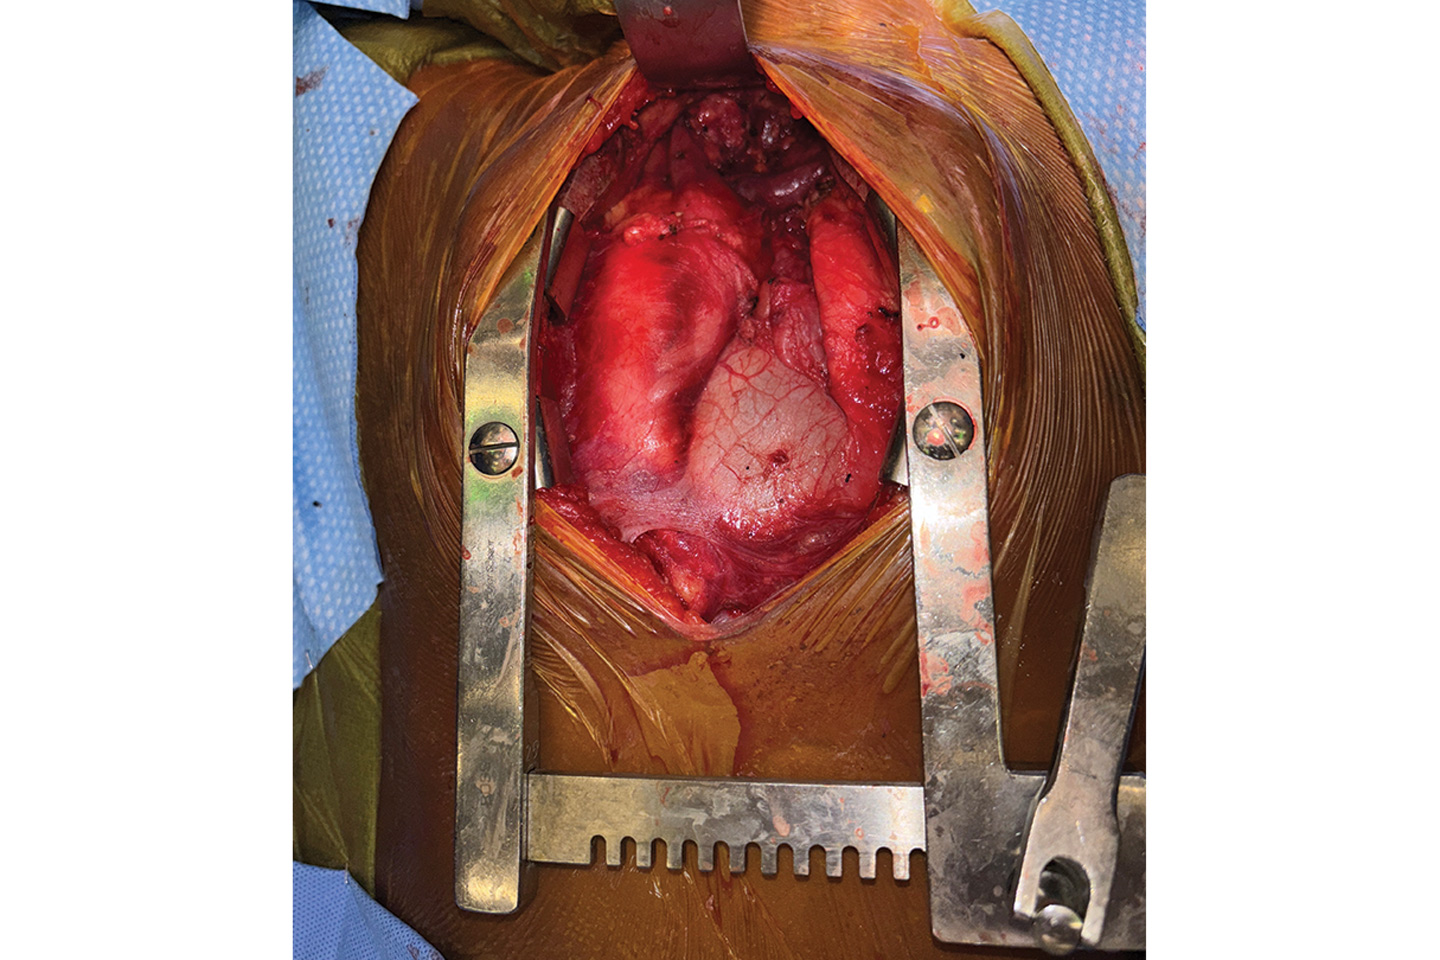

At a multidisciplinary tumor conference, a median sternotomy was chosen as the best operative approach. It would enable complete resection through a single chest incision and avoid the need for a separate incision at the neck. Jason C. Fisher, MD, a pediatric surgeon, and T.K. Susheel Kumar, MD, a congenital heart surgeon at Hassenfeld Children’s Hospital, prepared to address the cardiothoracic component.

Intraoperatively, the best-case scenario emerged: no tumor attachment to the brachiocephalic vein or invasion into the thyroid. “But we were prepared for all of these eventualities,” Dr. Duvvuri says.

“We were able to provide complete tumor resection with the least morbidity and all of the emergency options available,” Dr. Fisher says. “That outcome underscores the strength of our children’s hospital and the expert collaboration among our disciplines.”

Intraoperative image showing the tumor at the top of the incision. Source: NYU Langone Health.